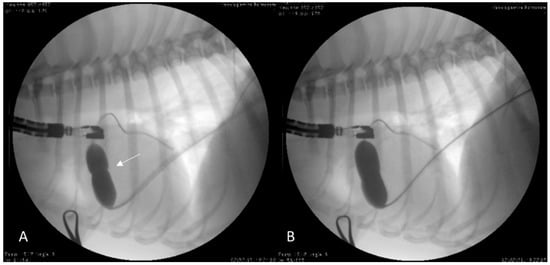

2.1. Case 1